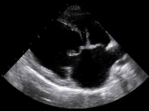

L’ecocardiografiadoppler ha l’obiettivo di consentire la valutazione morfo-funzionale della valvola, la determinazione della severità del rigurgito e la funzionalità del ventricolo sinistro.